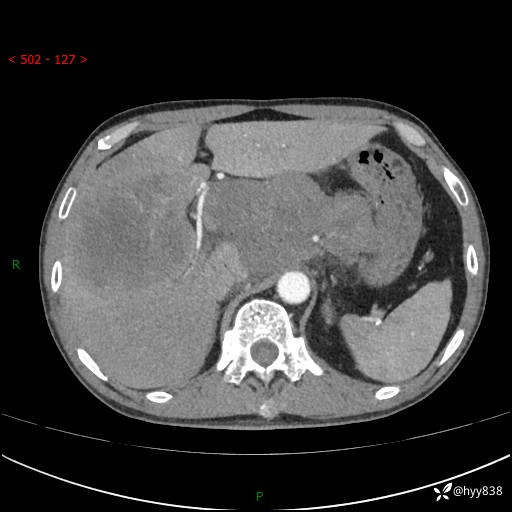

上腹部CT平扫+增强(两期)